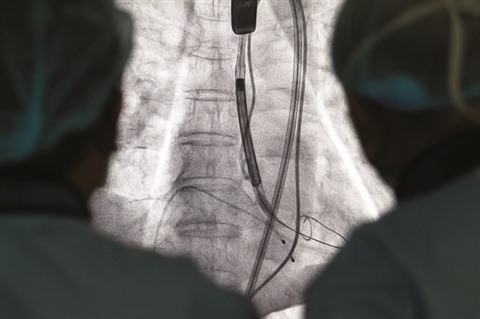

| Image de l’opération chirurgicale avec l’introduction percutanée de l’artère fémorale à l’aortectasie pour le remplacement valvulaire. |

Dans son cas, la meilleure solution consistait à recourir au remplacement valvulaire aortique par voie percutanée (TAVI), l’une des méthodes de remplacement de la valve cardiaque les plus modernes et compliquées au monde. Cette technique consiste à remplacer la valve aortique, par voie percutanée, en abordant l’artère fémorale. Ses avantages sont multiples : le taux de succès élevé, la diminution considérable du risque hémorragique et la limitation au maximum des complications postopératoires. De plus, la convalescence du patient est plus rapide, passant de deux à six jours seulement, contre une ou deux semaines pour une opération à cœur ouvert.